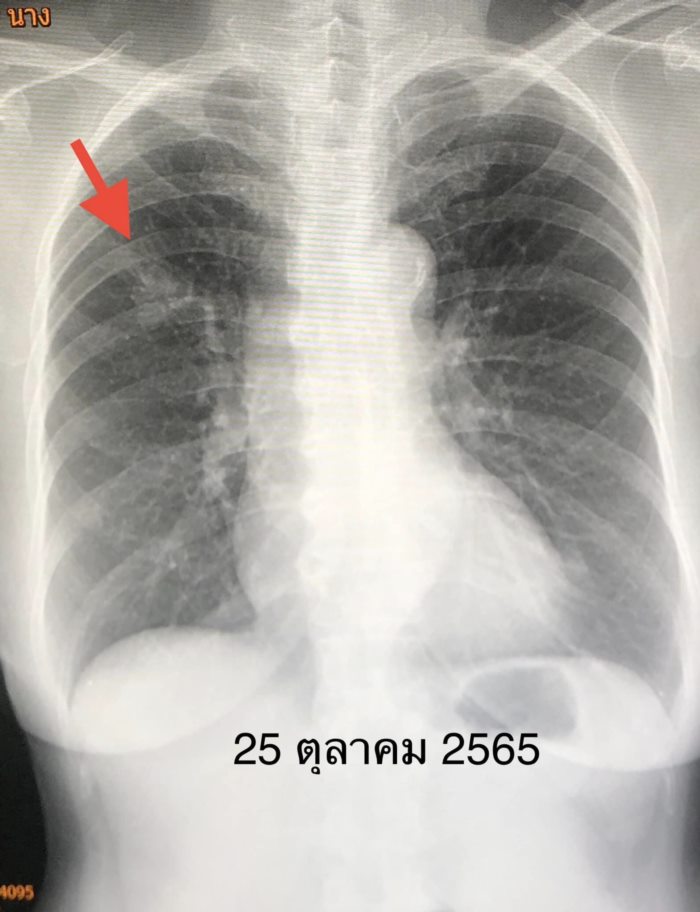

สรุปว่าป่วยเป็นมะเร็งปอดระยะแพร่กระจายแล้ว ผ่าตัดไม่ได้ เนื่องจากเวลานั้นยังไม่มียามุ่งเป้าที่ใช้กับยีนกลายพันธุ์ชนิดนี้ จึงได้เริ่มยาเคมีบำบัดตั้งแต่ต้นเดือนสิงหาคม 2565 โดยให้ยาเคมีบำบัด ALIMTA และ Carboplatin ทั้งหมด 8 ครั้ง ก้อนในปอด เดือนตุลาคม 2565 มีขนาดเล็กลง ต่อมาเดือนมกราคม 2566 ก้อนในปอดกลับโตขึ้นอีก เนื่องจากยาเคมีบำบัดใช้ไม่ได้ผลแล้ว